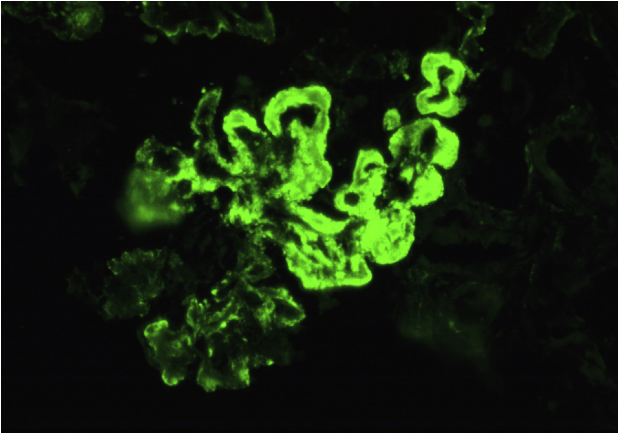

狼疮型肾炎Ⅴ型(膜性LN),弥漫性颗粒状沿着毛细血管环和系膜区染色(免疫荧光,IgG)。

狼疮型肾炎Ⅴ型(膜性LN),弥漫性颗粒状沿着毛细血管环和系膜区染色(免疫荧光,IgG)。